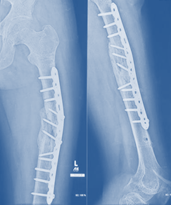

Thorough evaluation of patient was done and after 7 days of re-fracture, modified Ilizarov frame was mounted with plate in situ for treatment of the patient (Figure 4,5).

Figure 4 Post-operative x-ray after mount Ilizarov frame kept plate in situ.

The Ilizarov apparatus consisted of an arch in the proximal segment at the level of greater trochanter and full frame at lower 1/3rd of femur through two (2) rings. 1.5 mm schanz screws were used in arch and olive wires in distal rings. Figure 4 Accordion maneuver (AM) was started from 7th post-operative day of Ilizarov. We follow R. K. Baruah and S. Patowary protocol of accordion maneuver.